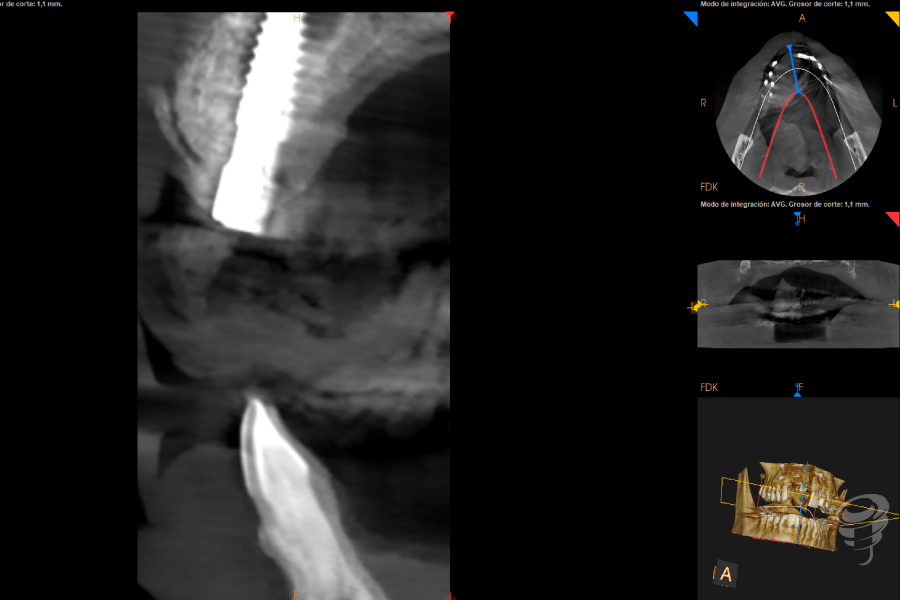

Realizamos un estudio con un CBCT de la zona. En los cortes seccionales se visualiza el implante en una posición muy vestibular, fuera del marco óseo y una imagen radiolúcida rodeando el implante.

Imagen 1

Imagen 2

Imagen 3